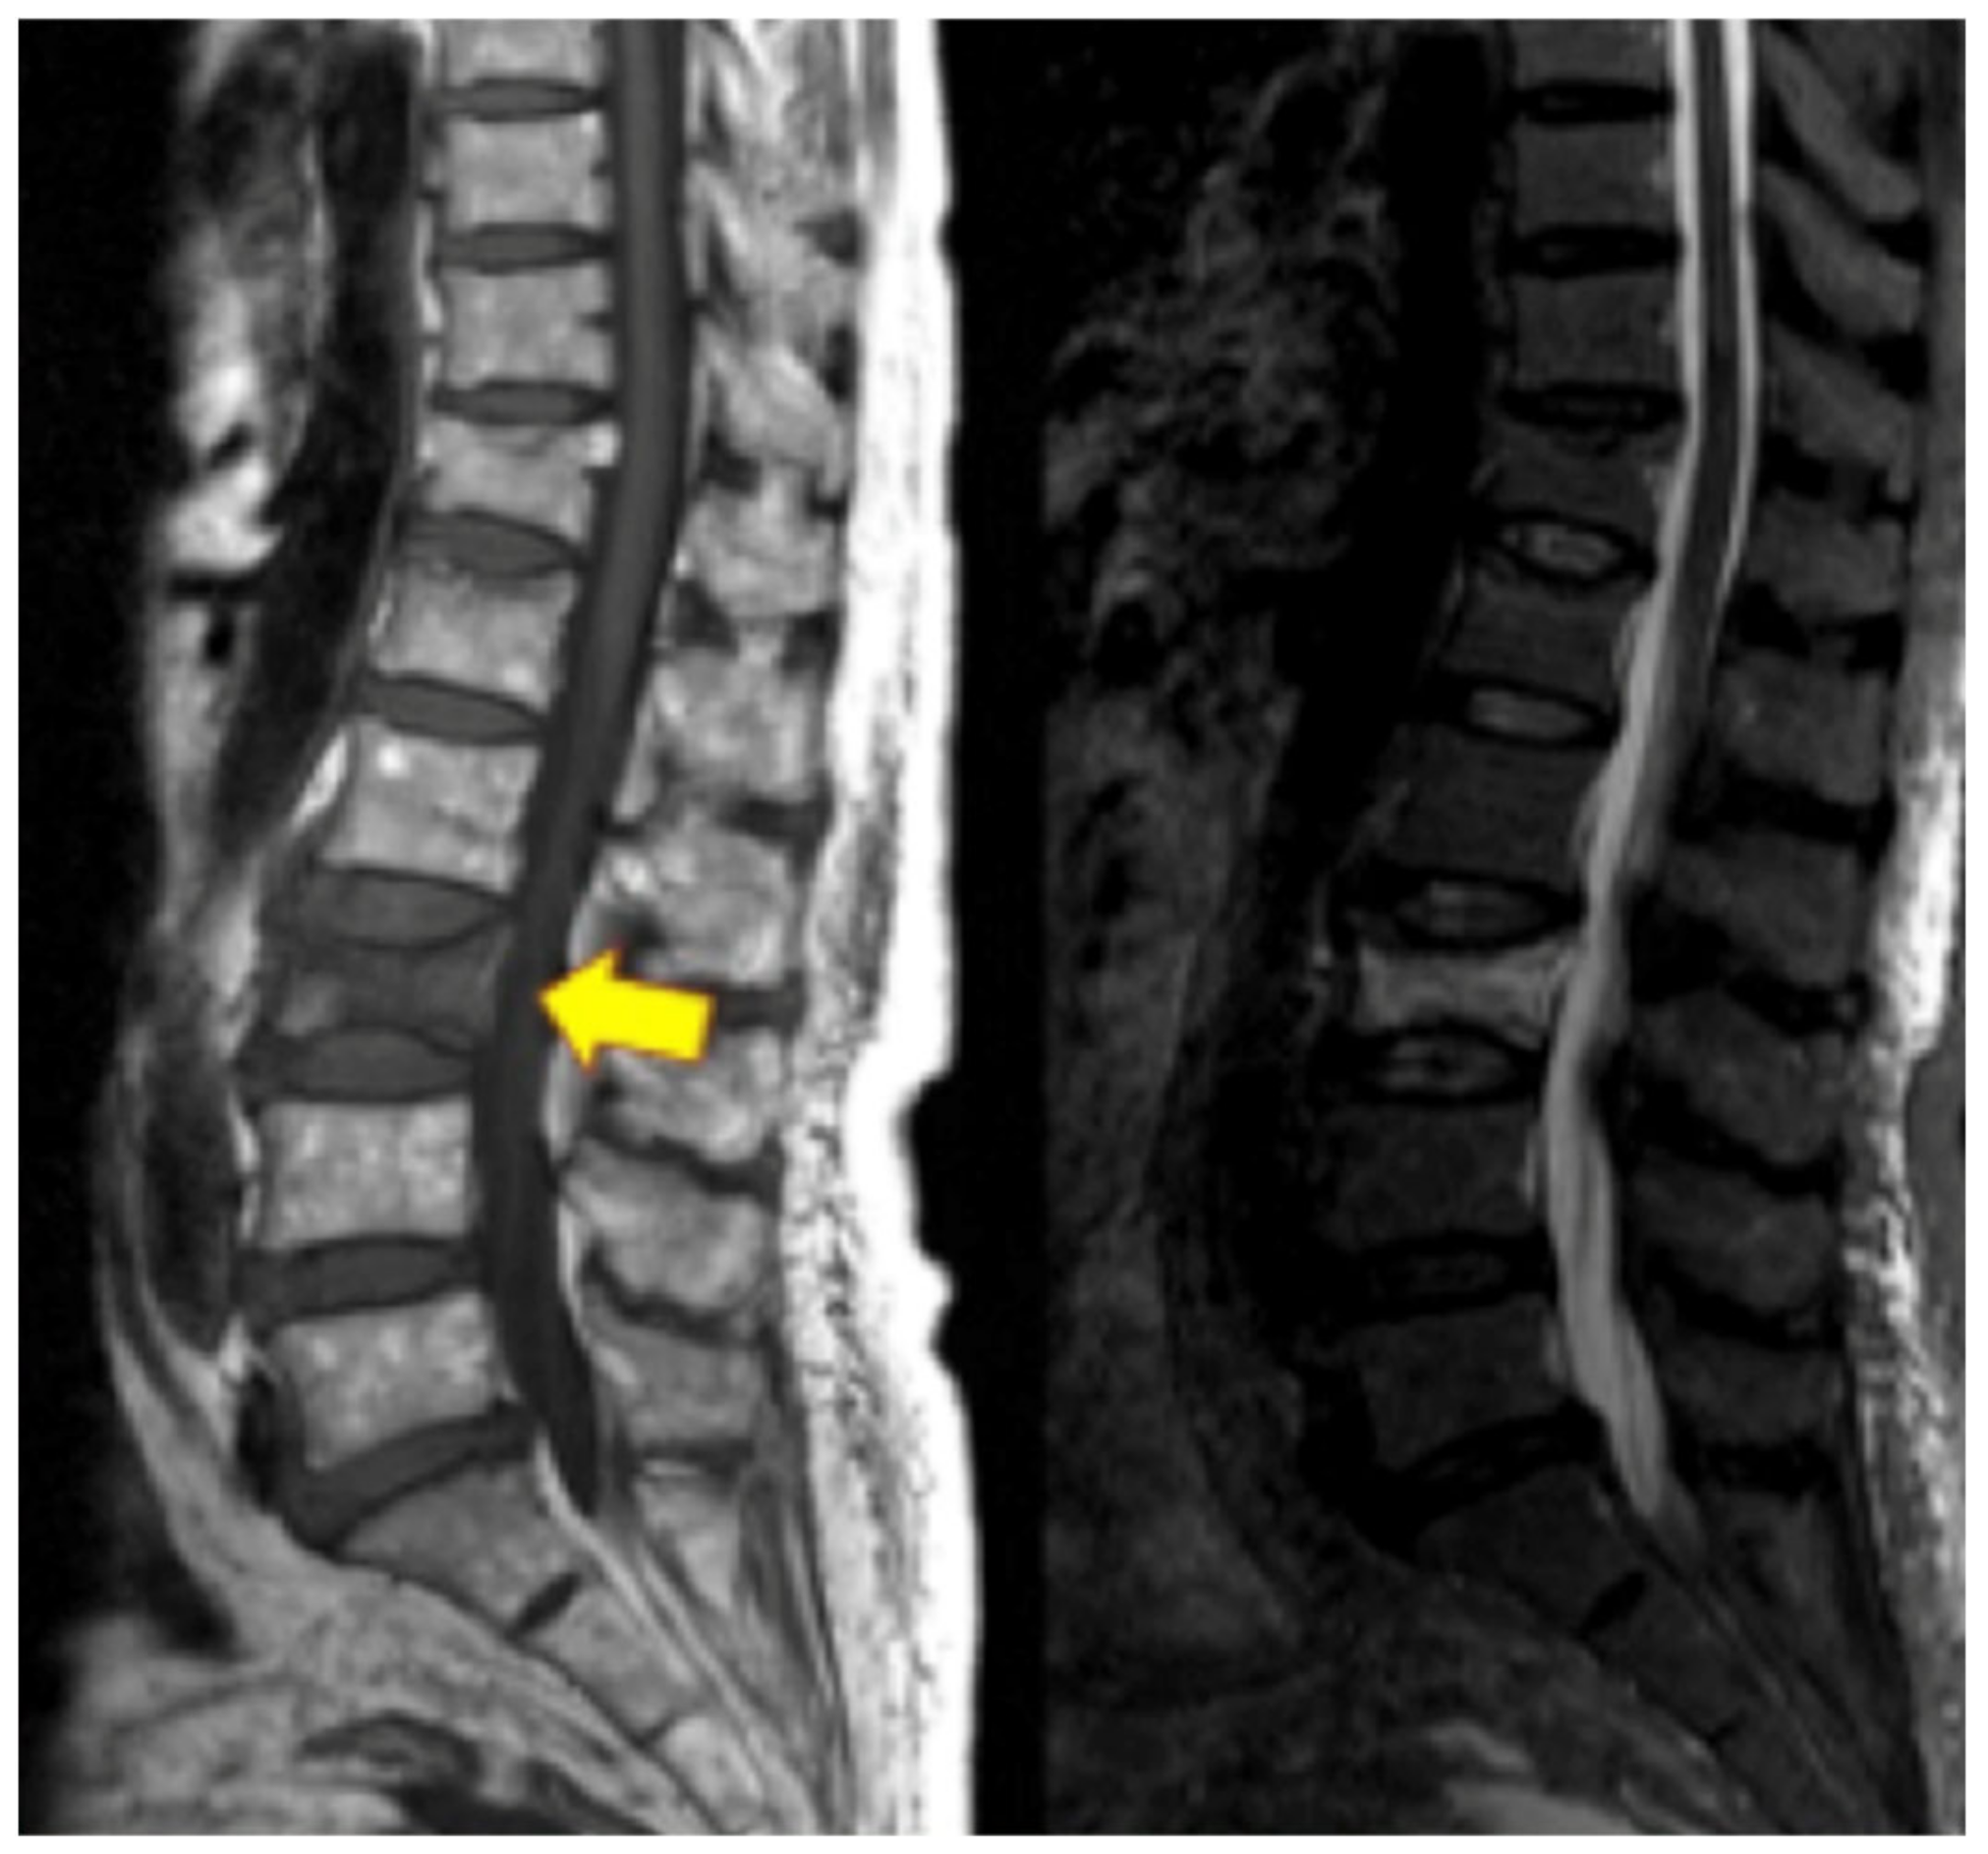

VFs may result from low-energy or high-energy trauma. Low-energy fractures are defined as fragility fractures, associated with decreased bone mineral density, infections, and cancer, while high-energy trauma is usually associated with high-impact axial loading with or without flexion, extension, or rotational components [87,88]. The most common etiology of VFs is osteoporosis; however, other etiologies include direct trauma, cancer, infection, steroids, chemotherapy or radiation, and other metabolic dysregulations [89]. Patients with VFs typically present with acute or chronic back pain, aggravated by prolonged standing, walking, or recurrent movements, and alleviated by rest and lying down. Additional symptoms depend on the spinal level of VF and whether it involves the anterior, middle, or posterior columns and the spinal canal, which, in this case, may include neurological findings. VFs may present with visible kyphotic deformity and increased pain with spinal percussion during physical exams [90]. At a minimum, thoracolumbar spine radiographs, including lateral, anterior–posterior, flexion, and extension, should be ordered if there is suspicion for VF. Additional diagnostic modalities include CT and/or MRI of the area to assess further bony detail, bone marrow edema, vertebral body height loss, etc. (Figure 4). These modalities are also more sensitive for early onset fracture compared to radiographs [91].

Figure 4.

Lumbar spine MRI on the left with yellow arrowing pointing at the L3 vertebral compression fracture. On the right is an STIR image of the L3 vertebral compression fracture with hyperdense bone marrow changes representing acute vertebral compression fracture.